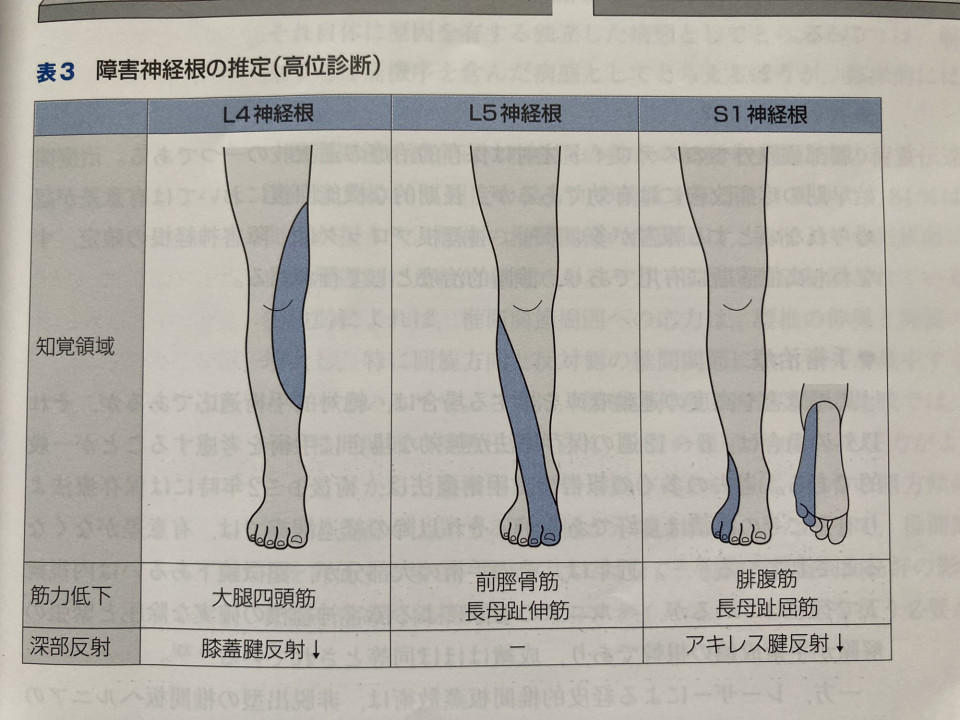

今日は腰椎5番目のヘルニアをした方が5ヶ月経っても症状が改善しないと言うのでリハビリしました。

主訴は脱力、評価をしたところL5の領域の前脛骨筋、長母趾伸筋の筋力が低く、

MMT(筋力テスト5がMAX)前脛骨筋が3、長母趾伸筋が4と低くなっていましたので神経の圧迫を解除する手技を行いました。

すると筋力は前脛骨筋4に回復し、長母指伸筋も4強に変わりました。

ヘルニアはほっといても治癒しますが、手を加えるとより回復しやすくなります。

患者さんも力がいきなり入るようになって「まるで手品みたい」と喜んでいただけてよかったです。